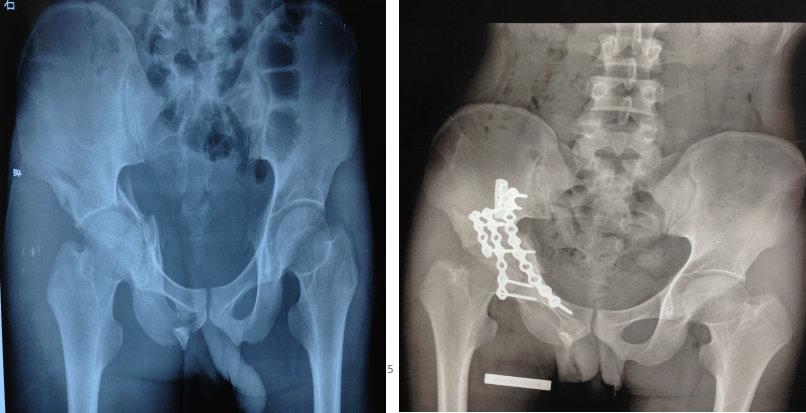

钛板内固定术治疗骨盆粉碎性骨折